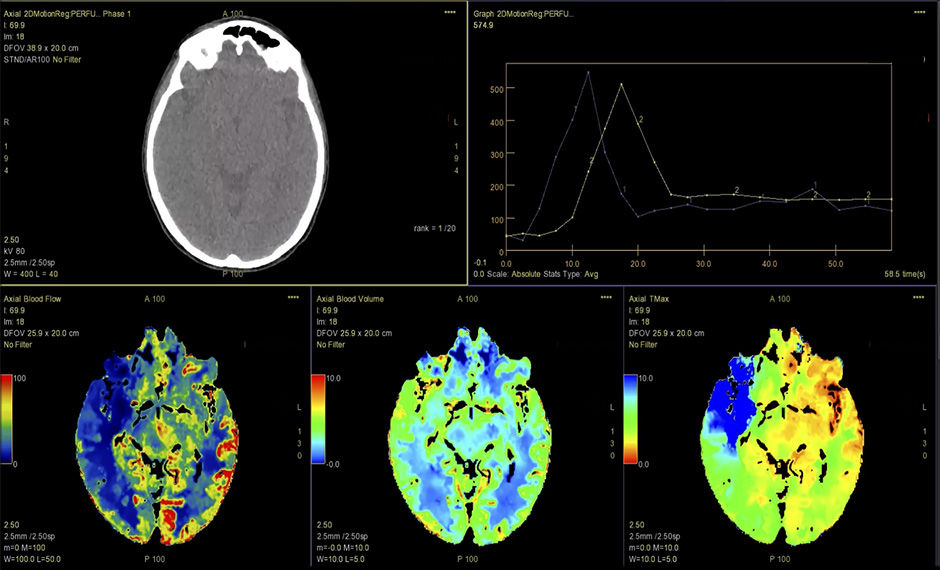

CT-Perfusion5

Automatisierte Perfusionsverarbeitung zur Erstellung von Funktionskarten.